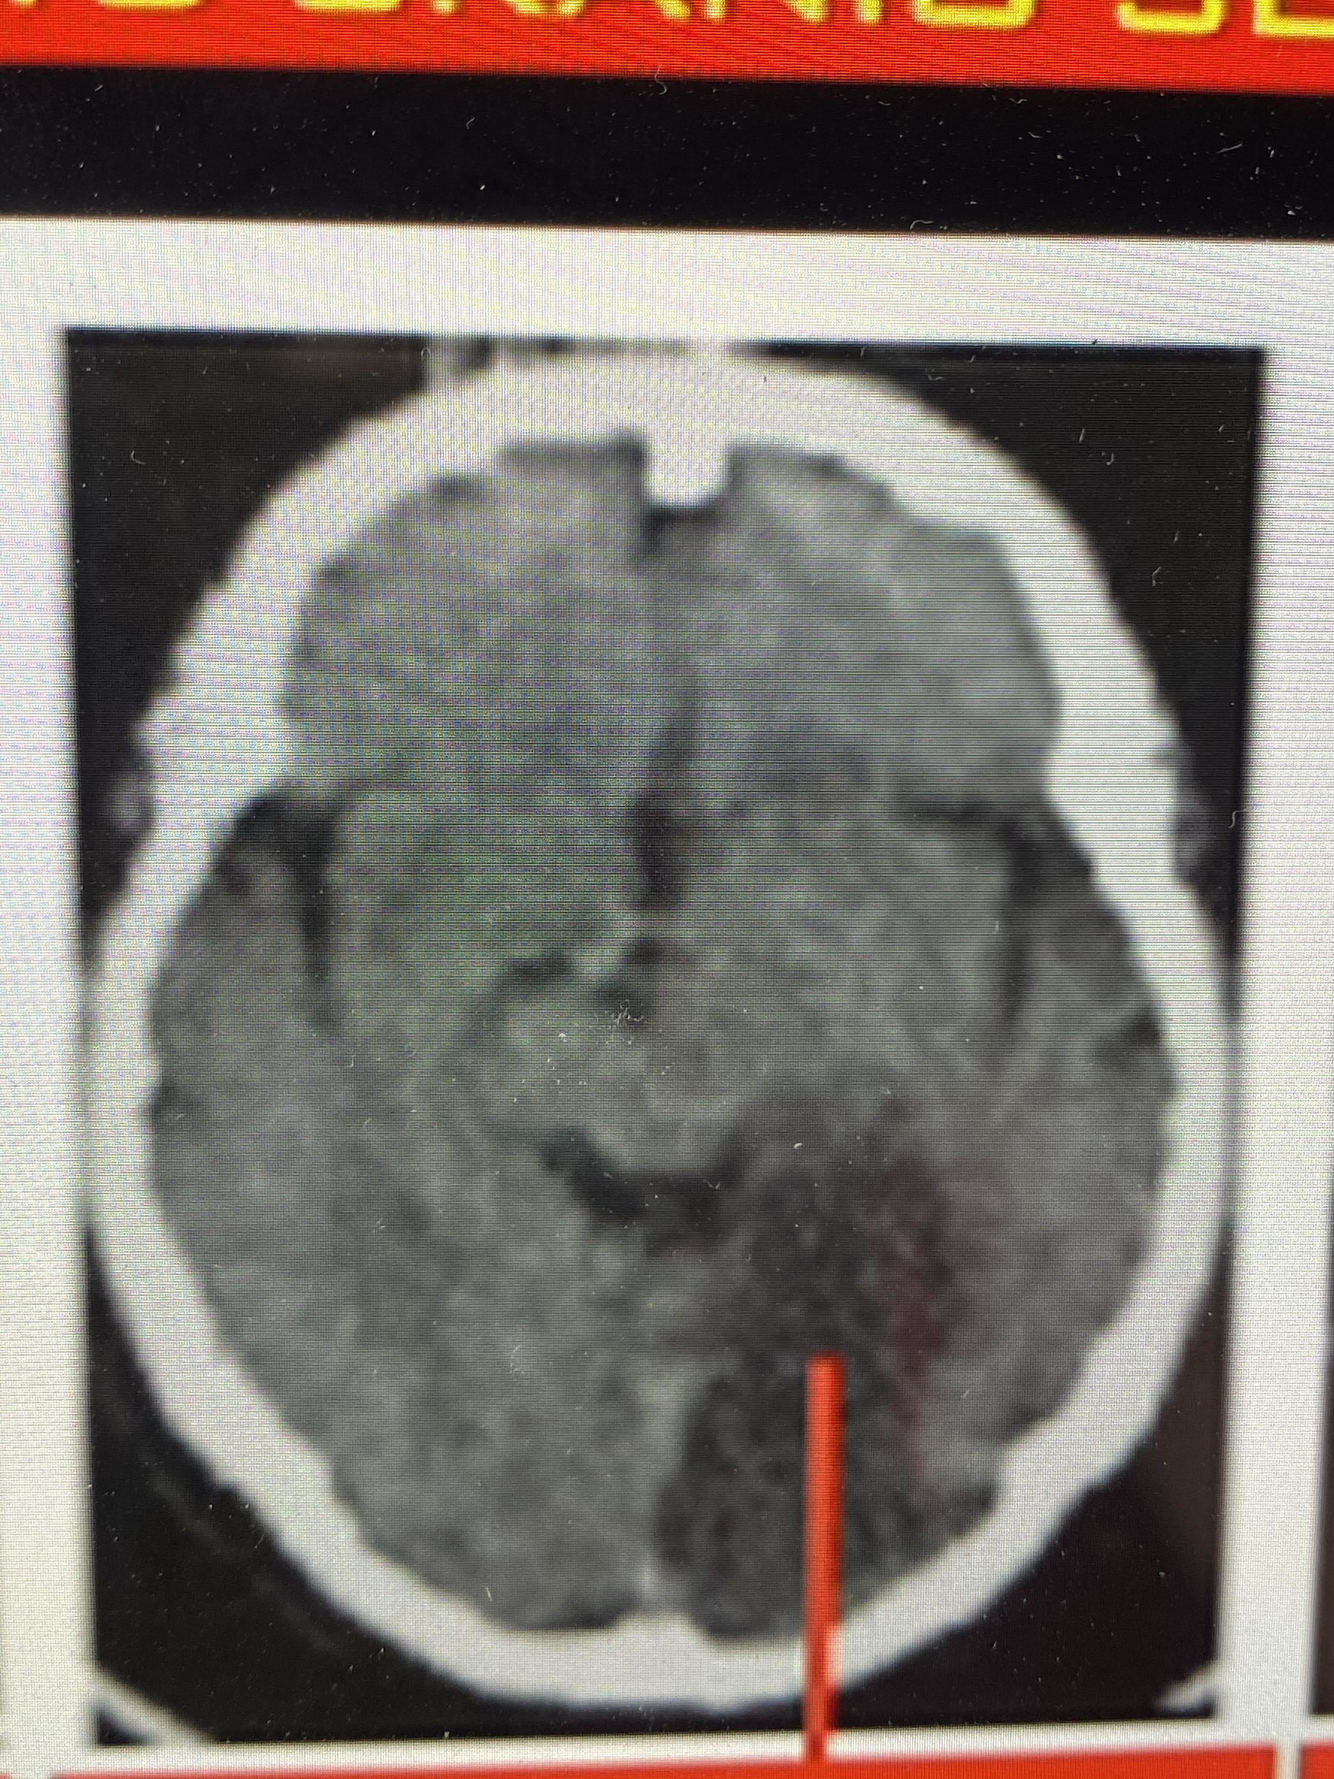

Qual artéria foi acometida?

A. Cerebral Anterior

A Artéria cerebral anterior acomete:

A parte MOTORA + SENSITIVA DA PERNA CONTRALATERAL